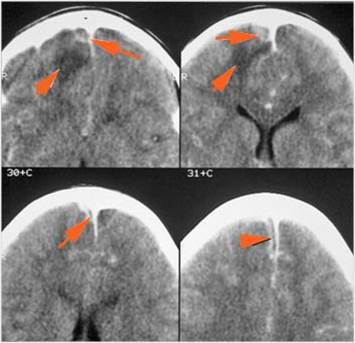

There is cerebritis specifically involving the frontal and temporal lobes. [Yes/No]

There is brain abscess specifically involving the frontal and temporal lobes. [Yes/No]